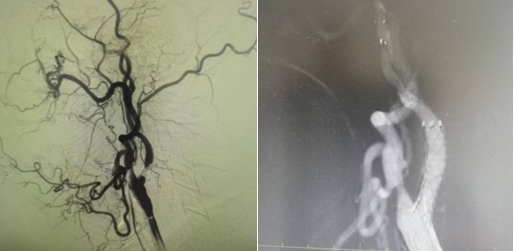

家屬同意后,神經(jīng)介入科團(tuán)隊(duì)迅速給予行腦血管造影,結(jié)果提示:右側(cè)椎動(dòng)脈重度狹窄。朱洪波副主任表示:該處一旦發(fā)生循環(huán)梗死,輕則癱瘓?jiān)诖?、重則昏迷不醒甚至危及生命,建議盡快對(duì)重度狹窄血管積極處理。家屬對(duì)患者病情及治療方案詳細(xì)了解后,決定接受介入手術(shù)治療。

手術(shù)在局麻下施行,通過(guò)經(jīng)橈動(dòng)脈入路,予以行右側(cè)椎動(dòng)脈起始處重度狹窄球囊擴(kuò)張術(shù),經(jīng)股動(dòng)脈穿刺,微導(dǎo)絲送入球囊至病變狹窄部位進(jìn)行擴(kuò)張,擴(kuò)張后造影提示狹窄部位擴(kuò)張滿意,基底動(dòng)脈血流明顯改善,手術(shù)順利結(jié)束。術(shù)后陳大叔上述癥狀完全恢復(fù),大叔妻子感激地說(shuō):“感謝國(guó)文醫(yī)院的積極救治,來(lái)的時(shí)候老陳都暈的無(wú)法走路,現(xiàn)在都能自己行走了,太感謝了。”

1個(gè)月前姜大爺(化名)反復(fù)出現(xiàn)右側(cè)肢體抽搐癥狀,碾轉(zhuǎn)當(dāng)?shù)囟嗉裔t(yī)院治療,效果不理想,嚴(yán)重影響日常生活,在家人的陪同下來(lái)到國(guó)文醫(yī)院神經(jīng)介入科。入院后給予行頭MRI彌散+頸部MRA提示:左側(cè)大腦半球分水嶺性腦梗死,左側(cè)頸內(nèi)動(dòng)脈起始處重度狹窄,給予行DSA提示:左側(cè)頸內(nèi)動(dòng)脈起始處重度狹窄至閉塞前改變。

丁金明主任指出:患者反復(fù)抽搐原來(lái)是血管狹窄惹得禍,跟患者家屬交代病情后,患者家屬要求血管內(nèi)介入治療,在導(dǎo)管室傾力配合下,順利完成“左側(cè)頸內(nèi)動(dòng)脈起始處重度狹窄支架植入術(shù)”,術(shù)后患者未再出現(xiàn)抽搐癥狀,術(shù)后在醫(yī)護(hù)人員的精心治療和悉心護(hù)理下,患者恢復(fù)良好即將出院。